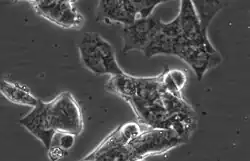

LAPC4 cells are a cell line of human prostate cancer commonly used in the field of oncology. The tissue was harvested from the lymph node metastasis of a male patient with hormone refractory prostate cancer which was then xenografted into SCID mice and later harvested and plated on tissue culture dishes, where it can be propagated as an immortalized prostate cancer cell line.[1][2][3]

LAPC4 are a lowly adherent, epithelial cell line with high Androgen receptor and Prostate specific antigen expression.[4] Unlike the other commonly utilized, Androgen receptor positive prostate cancer cell lines LNCaP and VCaP, LAPC4 have high expression of Keratin 5, a basal marker, as well as the luminal markers Keratin 8 and Keratin 18.[4] LAPC4 also expresses mutated P53 (R175H). [4]

The cells have an approximate doubling time of 72 hours under typical culture conditions.[5]